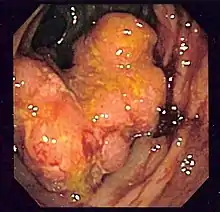

Endoscopic image of colon cancer identified in the sigmoid colon on screening colonoscopy for Crohn's disease